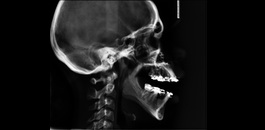

Indicada para realização de análises cefalométricas. Sendo possível a avaliação das estruturas ósseas e respectivas interrelações. Muito indicada para planejamentos ortodônticos e ortopédicos.

Avaliação das vias aéreas.